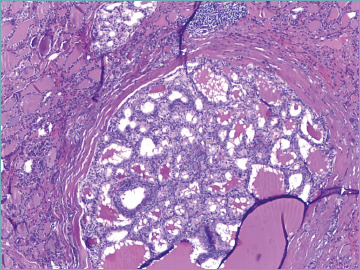

目的:美国甲状腺协会(ATA)更新了甲状腺癌治疗指南,根据临床病理特征采用了一种不那么激进的方法。因此,与全甲状腺切除术相比,行肺叶切除术的可能性显著增加。大多数甲状腺癌是惰性的,预后良好,而只有15%的高分化癌(包括乳头状甲状腺癌(PTC))患者在诊断时为局部晚期甲状腺癌(LATC)。我们回顾了过去十年来治疗甲状腺癌的实践。方法:对2010年1月至2020年12月1057例甲状腺单发良、恶性病变患者进行回顾性分析。结果:77%为女性,中位年龄49.3岁。307例恶性诊断(29.05%),其中经典PTC 196例(61.6%),侵袭性PTC 38例(12%),多为高细胞变异(30例,9.4%)。在恶性病例中,显微镜下发现84例(26.4%)为多灶性病变。采用ATA风险分布,低危239例,中危68例。第二次手术共对150例患者进行了评估,显示42例患者在另一侧肺叶有额外的甲状腺癌灶(26例单发灶vs 16例多发灶)。甲状腺周围淋巴结转移10例。结论:我们的数据可以作为进行纵向研究的基础,以确定哪些危险因素可以预测双侧受累,并建议量身定制的手术方法。

Results: Among these cases, 77% were women with a median age of 49.3 years. The series involved 307 malignant diagnoses (29.05%) including 196 (61.6%) classic PTC and 38 (12%) aggressive variants of PTC, mostly tall cell variant (30 cases, 9.4%). Among malignant cases, multifocality was microscopically documented in 84 cases (26.4%). Using the ATA distribution of risk, there were 239 cases in the low risk and 68 in the intermediate risk categories. Second surgery was assessed in a total of 150 cases, showing 42 cases with additional thyroid cancer foci in the other lobe (26 single vs 16 multiple foci). Ten cases had metastatic perithyroidal lymph nodes.